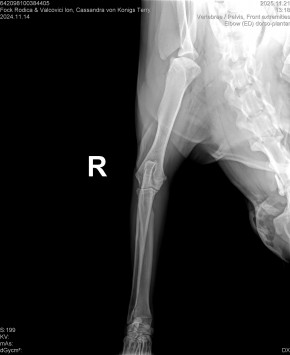

CASSANDRA VON KONIGS-TERRY

( CASSY )

Data nasterii:

14.11.2024

FOCK RODICA si VALCOVICI ION